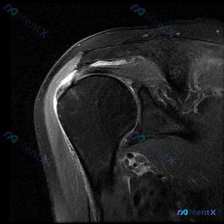

刚整理完一份肩部MRI读片病例,病例本身不复杂,但很容易只看到表面的积液忽略根本问题,分享给大家,整理一下完整的分析思路。 病例影像基础信息 本次读片基于肩部MRI-T2序列冠状位影像,核心初始发现是软组织积液,我们来逐层拆解: 影像学客观发现 1. 冈上肌肌腱:在肱骨大结节附着点(足印区)区域,肌...